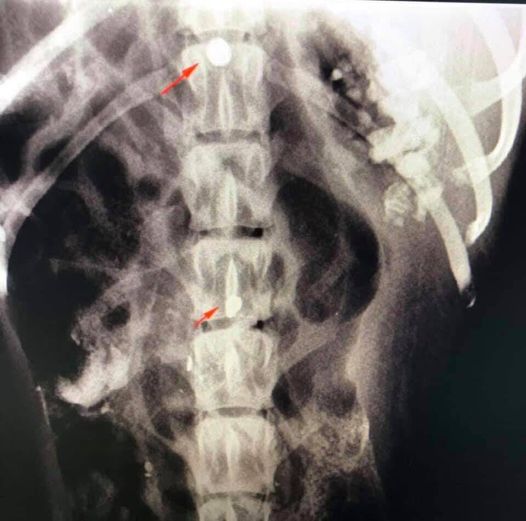

He named him Cuko, and they took him to the Vet.The X-ray showed that this Cuko was literally riddled with a sackcloth! That he literally survived the shootout!

A large number of sacmi was found in it with an X-ray. And unfortunately two of them ended up in the back column! The veterinarian assessed that he could perform the surgery and try to remove the sac from his nose and get the bullet out of his spine.. Of course, no one wants to make forecasts!